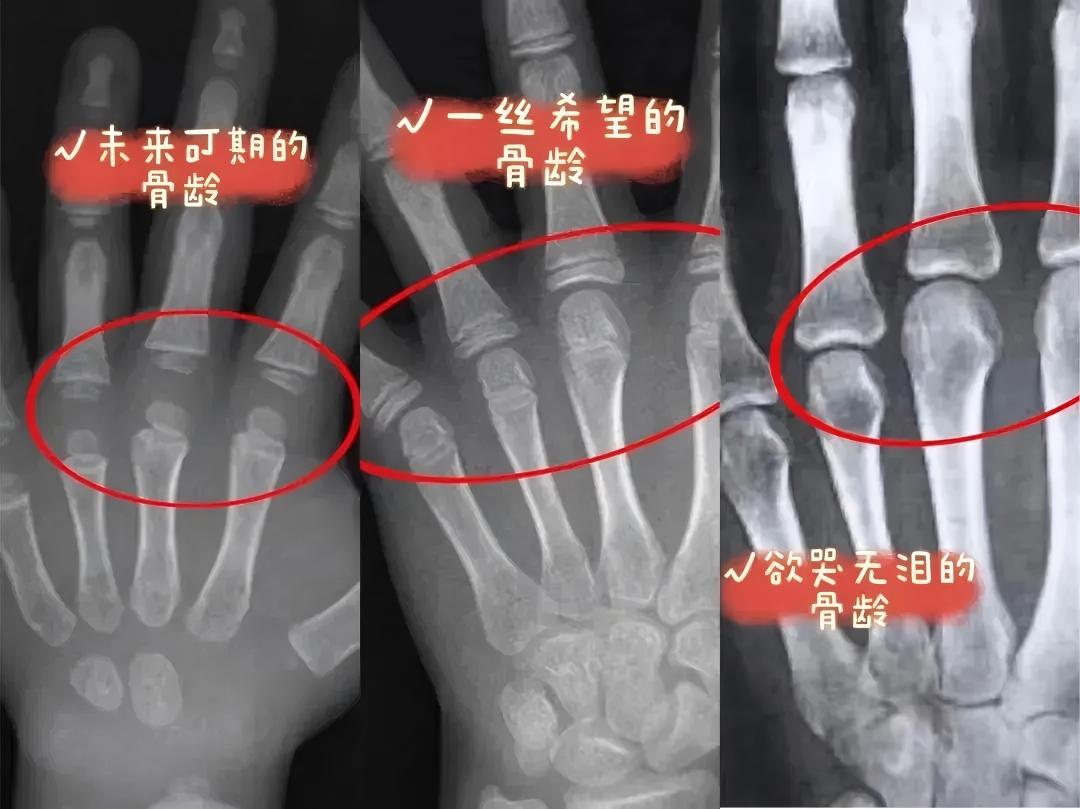

其实,一个孩子的身高还有没有生长潜能、还有多少身高可长,从手骨片上都是能够比较明确地看出来的。当一个孩子手指尖的成长板都融合了,其他部位的成长板还没有融合,这个孩子的平均身高生长潜能一般只有5厘米了,这时候男孩的骨龄一般为14岁,女孩的骨龄一般为12岁。